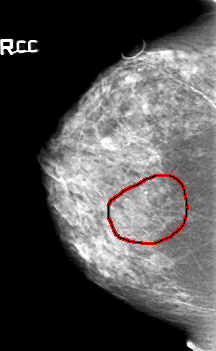

FILE: D_4154_1.RIGHT_CC.OVERLAY

TOTAL_ABNORMALITIES 1

ABNORMALITY 1

LESION_TYPE CALCIFICATION TYPE AMORPHOUS DISTRIBUTION SEGMENTAL

ASSESSMENT 5

SUBTLETY 3

PATHOLOGY MALIGNANT

TOTAL_OUTLINES 1

BOUNDARY